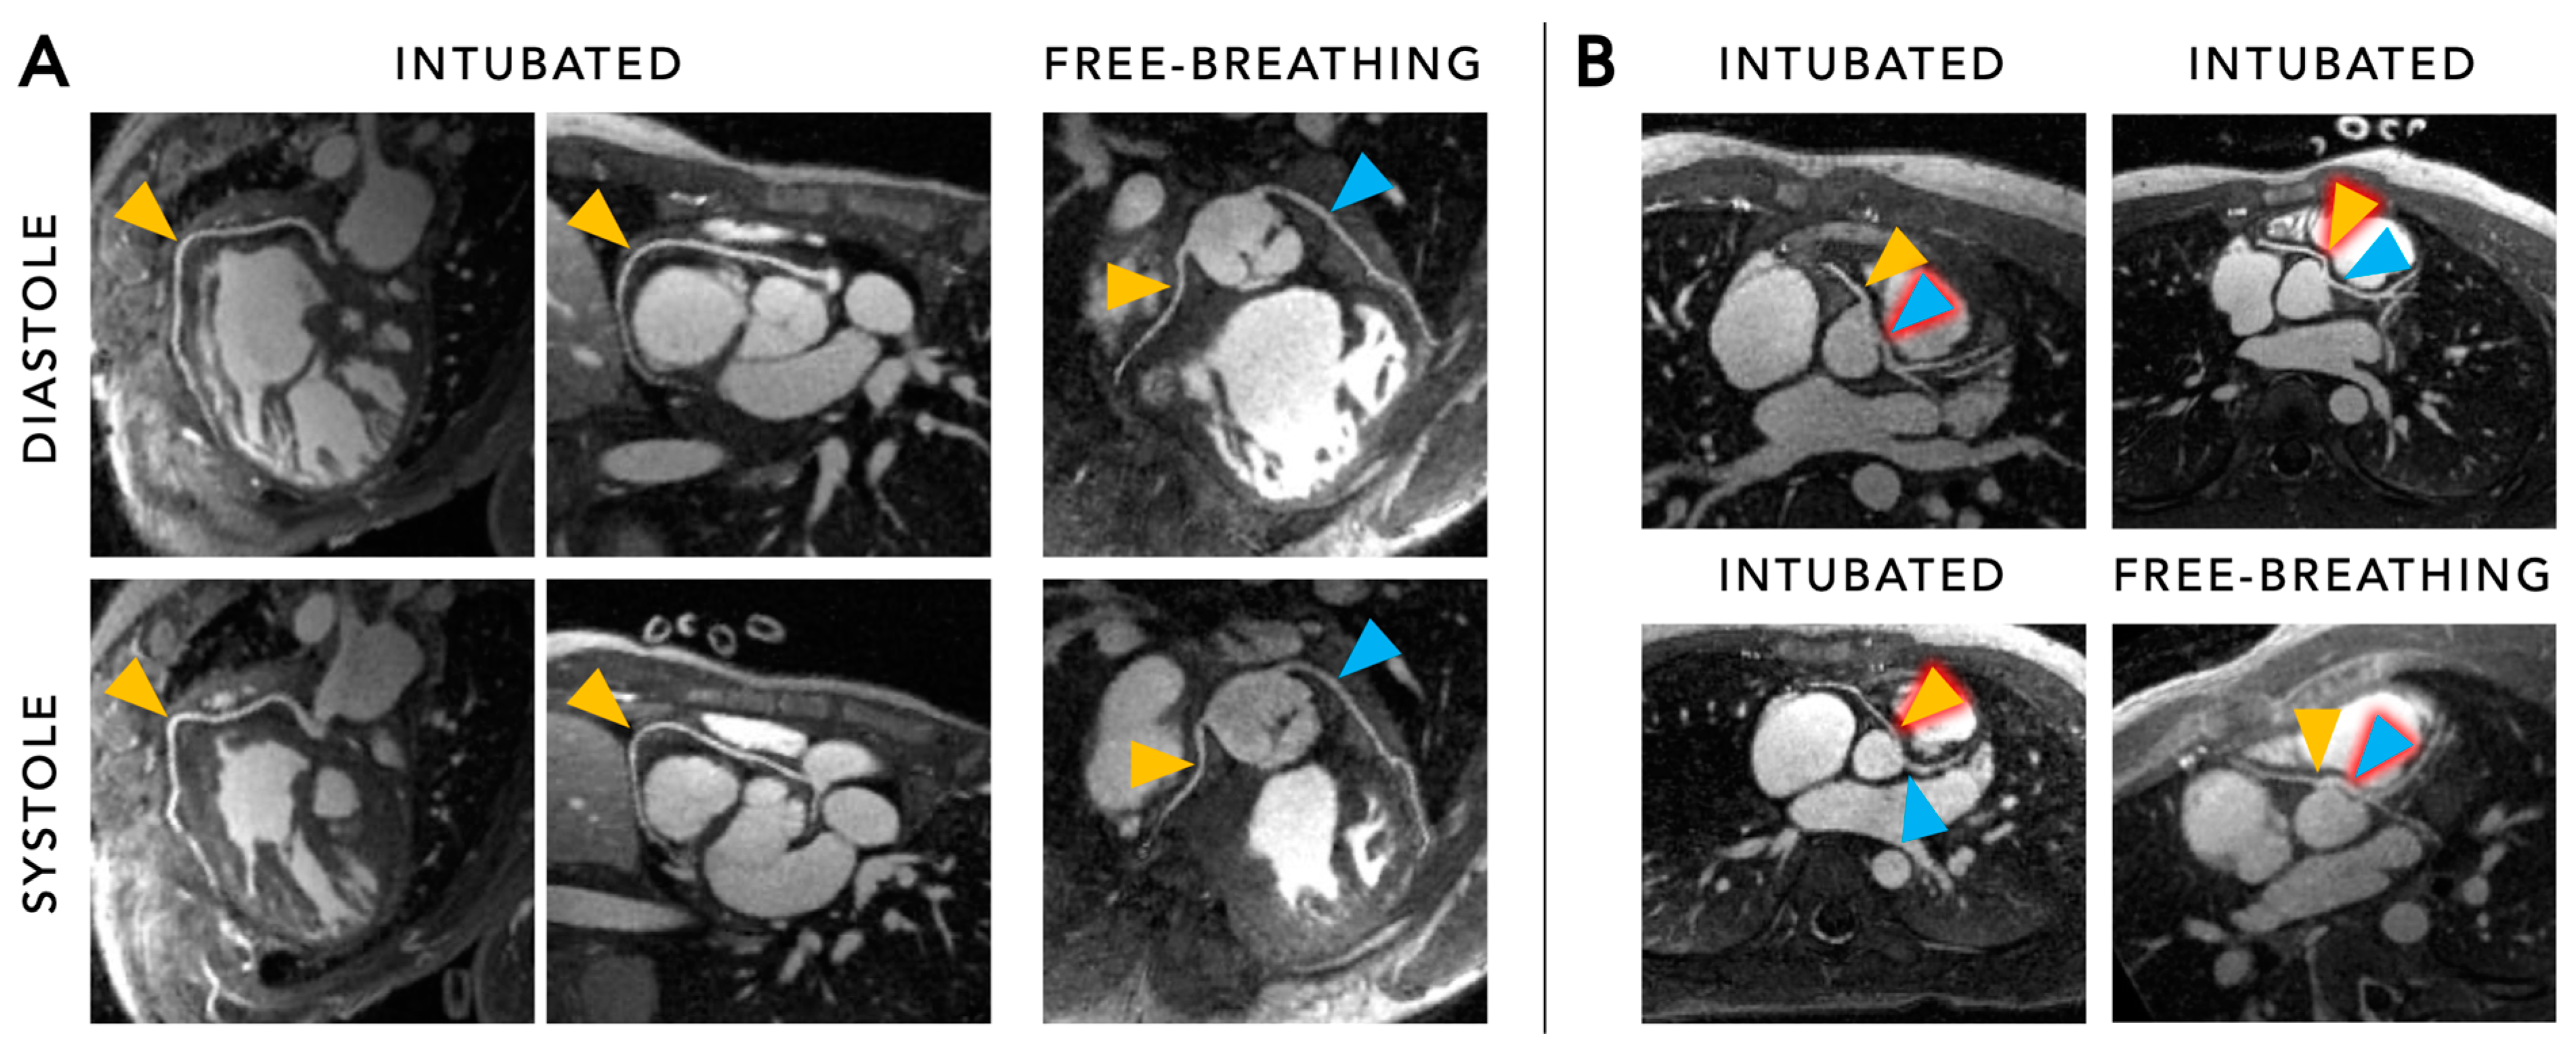

5.2. Functional Cine Imaging

5.3. Flow Imaging